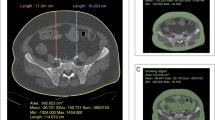

The surgery was performed by two experienced obstetricians and gynecologists with specialized training in vNOTES and one assistant surgeon from Qinghai Red Cross Hospital. Under general anesthesia, the cervix and posterior vaginal fornix were exposed, and a vasopressin solution (0.12 U/mL) was injected at the junction of the cervical and posterior vaginal wall mucosa to separate the vaginal rectal space. A 2 cm arcuate incision was made at the top of the posterior fornix, the rectum was bluntly separated, and the peritoneum at the rectouterine pouch was opened to access the pelvic cavity. A port was installed, and pneumo-peritoneum was established with an intraoperative pressure maintained at 8–10 mmHg. The remainder of the procedure followed MPLS protocols. The resected specimen was removed transvaginally, and the peritoneum and vaginal wall were sutured with absorbable stitches. An iodine-soaked gauze was placed inside the vagina and removed after 24 h. (see Fig. 1).